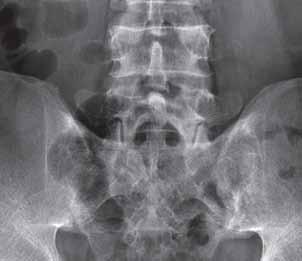

Rycina 2.12.

Przystawowy zanik kostny na poziomie stawów MCP ręki L.